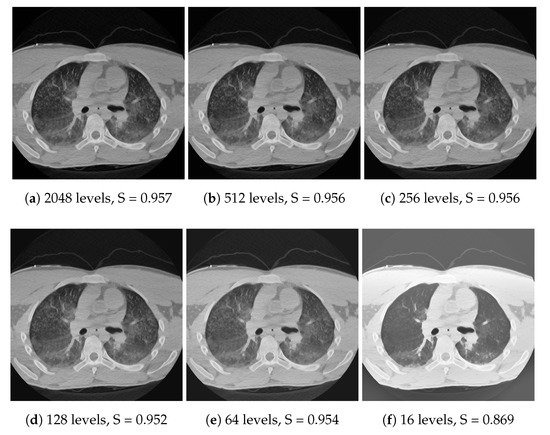

Both spatial downsampling and dithering build on the fact that important features in the images usually have a larger area than a few pixels, and the local histograms do not change too fast; therefore, the 3D histogram can be approximated well with one which has reduced resolution along all axes. As long as these assumptions are valid, the tone mapping can approximately linearly speed up with downsampling in terms of the number of pixels and/or shades. Memory consumption scales down in a similar manner. The effect of the techniques can be seen in Figure 11 and Figure 12 for dithering and downscaling, respectively. Note that the downscaling is meant for each axis. For instance, a 64× downsample means only eight samples along each axis, and 64 samples in total for a CT image with 512 × 512 pixels.

Figure 11.

Calculating the histograms using a decreasing number of discretization levels. While quality slightly degrades after a while, the linear interpolation and dithering make the algorithm robust. TMQI structural similarity slowly decreases as the approximation becomes coarser.